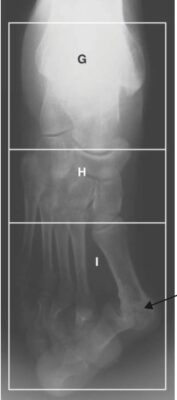

LIÊN HỆ X QUANG

Ghi chú chữ viết tắt:

- G = Hindfoot; Bàn chân sau

- H = Midfoot; Bàn chân giữa

- I = Forefoot; Bàn chân trước

- A = Ankle; Cổ chân

- C = Calcaneus; Xương gót

- Cu = Cuboid; Xương hộp

- T = Talus; Xương sên

- N = Navicular; Xương ghe

- S =Spur; gai xương (gót)

- MT = Metatarsal; xương bàn